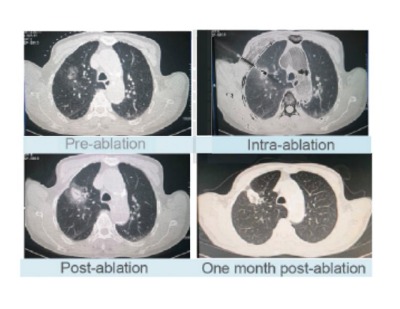

Advantages of Microwave Ablation on lungs

• High thermal efficiency :

Fast ablation speed and wide ablation zone

• Application :

Both for peripheral and central lung nodules, cancer,GGO

• Minimally invasive treatment :

Minimally invasive, local inactivation, organ function preservation, less complications, to improve " life quality of patients" wide ablation

• Combined therapy :

It can be combined with surgery, radiotherapy and chemotherapy to improve the curative effect